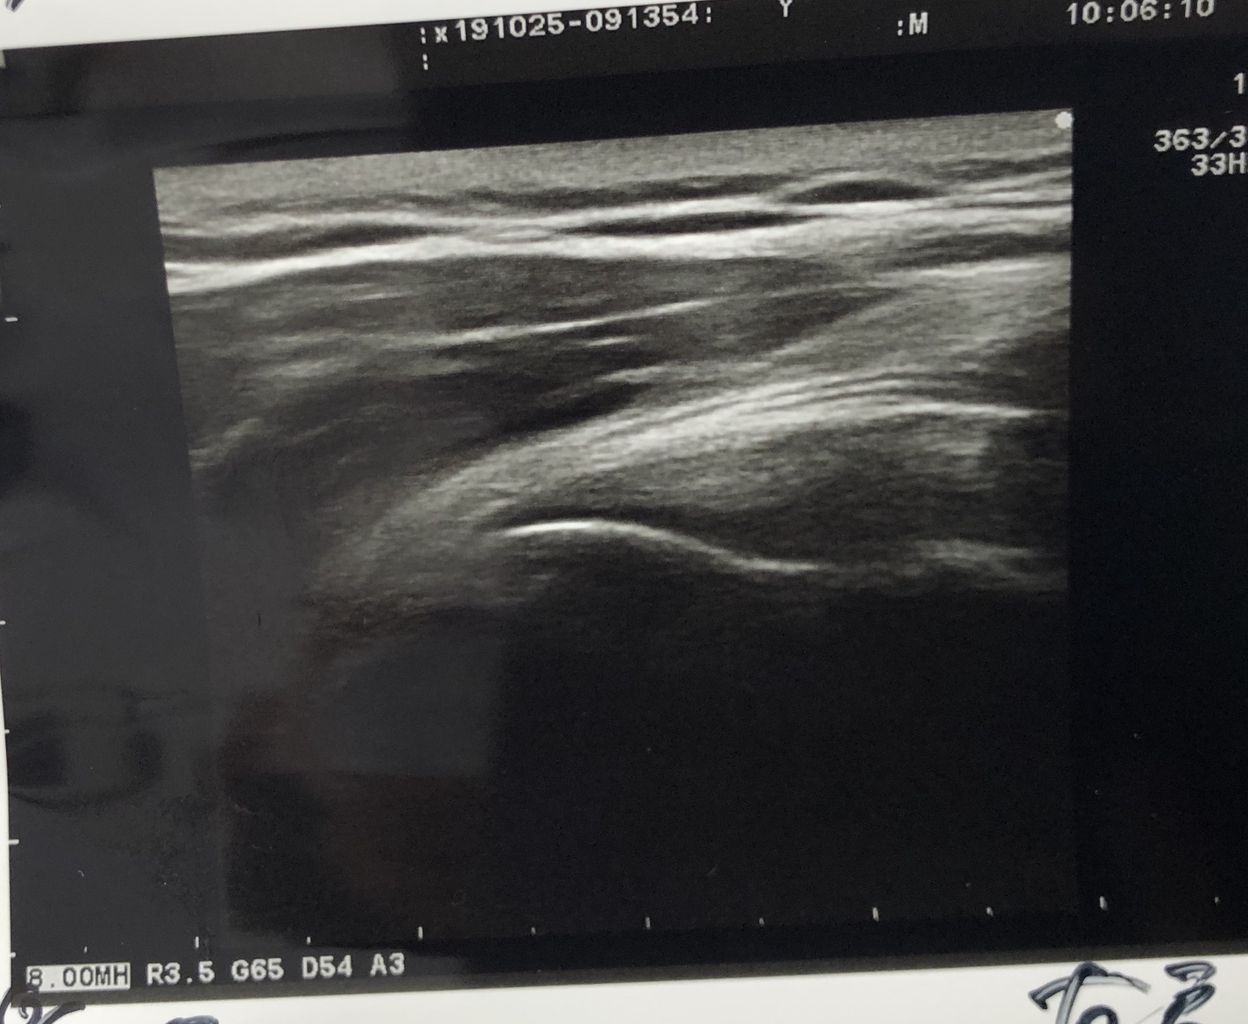

投球肩の違和感があり来院です

肩甲骨まわり股関節まわりの指導

をしたら痛みは解消しました